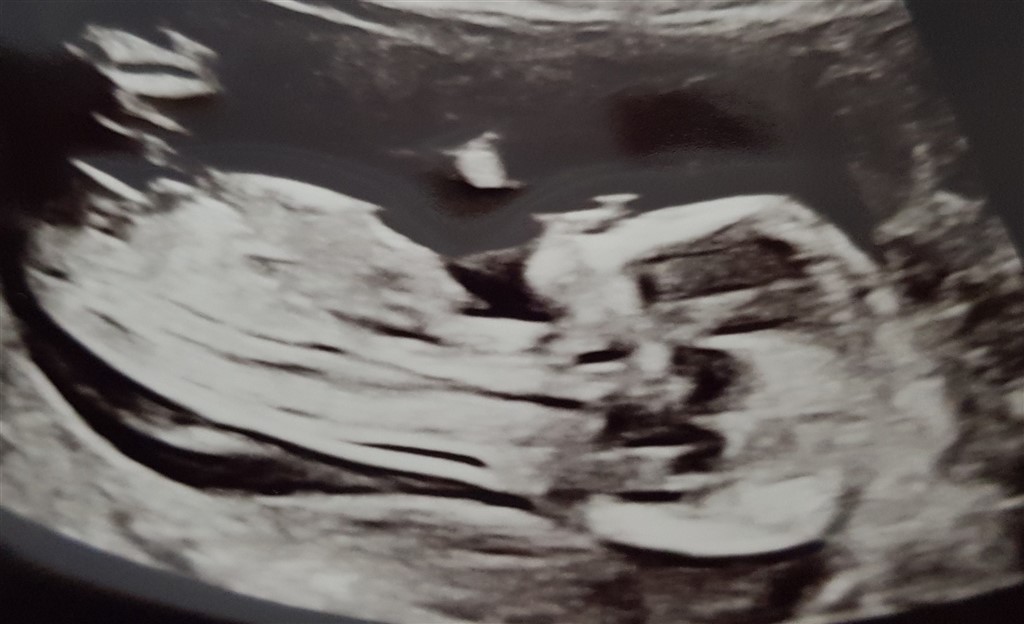

Jeg er så ulykkelig og ked af det! Jeg var til nf scanning i sidste uge og fik nogle fine billeder med hjem. Nubben på billedet lignede først for mig en dreng og var så lykkelig fordi jeg havde et brændende ønske om en lillebror til min datter. Hun har faktisk gået rundt og sagt lillebror før jeg overhovedet var gravid, bare ud i det blå.

Men jo mere jeg studere billederne kan jeg godt se det ligner en pige! Og jeg er så ked af det, som om min verden er brudt sammen!

Kan nubben nå at rejse sig? Eller er den færdigudviklet 13+3? Nogen andre som har fået modsatte køn selv om nubben viste noget andet?

Det var meget svært at få baby til at ligge stille. Hver gang vi forsøgte at tage billeder gemte baby sig længere og længere væk. Og en gang efter damen havde prøvet at banke på min mave flere gange sagde hun han er godt nok stædig, så jeg blev nærmest 95% sikker på det var en dreng. Men når jeg studere billederne mere og mere og ser ændres og sammenligner så er jeg blevet så trist

Man siger det først er efter 14+0 man kan være sikker på om den har rejst sig eller ej.

Prøv at lægge billedet op. Der er intet i vejen med at ønske et bestemt køn, og lige gyldigt om udfaldet skal du nok ende med at være en perfekt mor for barnet.

Jeg lægger billede ind, ud fra nubben virker den vandret, men hovedet virker kantet. Er så meget i tvivl.